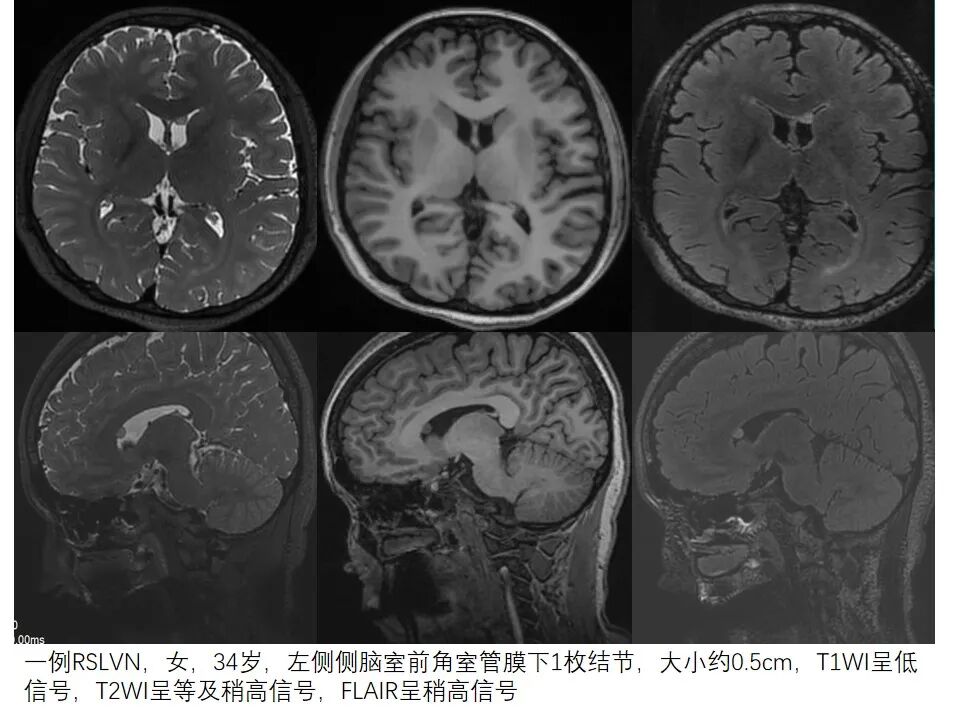

一例RSLVN,女,34岁,左侧侧脑室前角室管膜下1枚结节,大小约0.5cm,T1WI呈低信号,T2WI呈等及稍高信号,FLAIR呈稍高信号